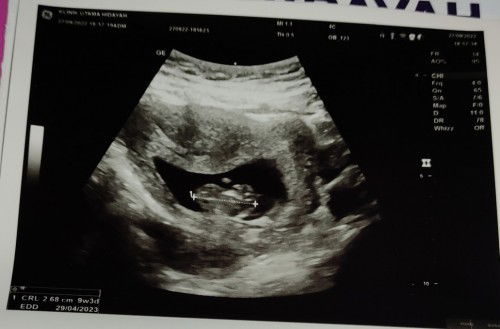

Hasil USG beda

Usia menurut hpht 11w2day .. Usg 9w3day ..Aku si gak worry bun karna katanya yang penting jarak gak 2wk lebih. Kata dokter juga gakpapa terus bilang coba kita lihat lagi 1bulan lagi . Tapi bunda2 disini ada yang ngalamin sama gak si ? Atau kebanyakan memang berbeda gini ? Tapi ada gak si yang bener2 tepat sama hpht bun?